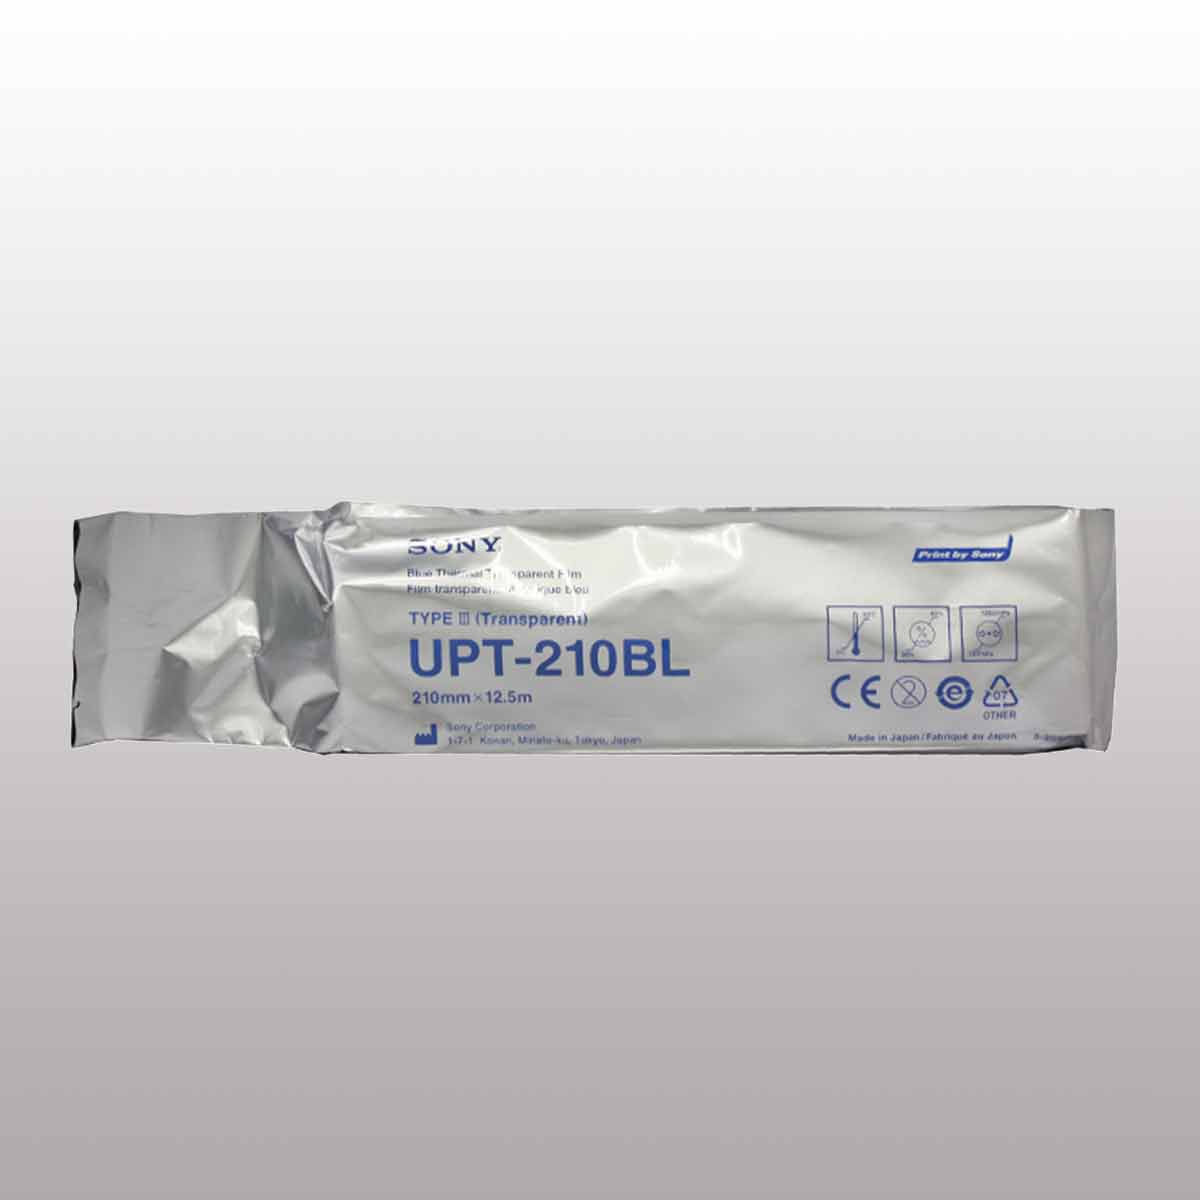

فیلم حرارتی آبی شفاف UPT-210BL

فیلم حرارتی شفاف سونی با کیفیت و وضوح عالی برای پرینترهای هیبریدی UP-991AD، UP-990AD و UP-980AD مناسب است. همچنین، فیلم حرارتی آبی شفاف UPT-210BL با ابعاد ۴۹۲×۱/۴ ۸ اینچ (۱۲۵۰۰×۲۱۰ میلیمتر) برای چاپ تصاویر با کیفیت بالا در پرینتر پزشکی UP-990AD قابل استفاده است. هر رول این فیلم برای گرفتن ۴۲ پرینت مناسب است.

| Blue Thermal Transparent Film | Type of Media |

| 210mm×12.5m | Contents |

| 210mm×12.5m (8 1/4×492inches) | Paper/Film Size |

| Approximately 42 Prints | Print Pages for One Roll |

| UP-991AD, UP-990AD, UP-980AD | Supported Printers |